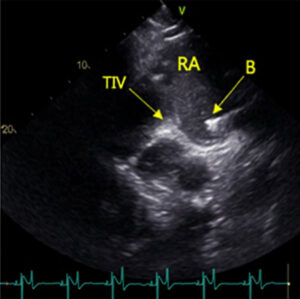

Gennem et kateter i halsvenen føres et bioptom (B) ned i højre atrium, hvor der udtages en

knappenålsstor vævsprøve. Da der ikke findes smertereceptorer i hjertevæggen, mærker hesten

ikke selve udtagningen.

Proceduren guides med ultralyd, mens bioptomet føres ned i højre atrium (RA), åbnes og tager

væv fra tuberculum intervenosum (TIV).